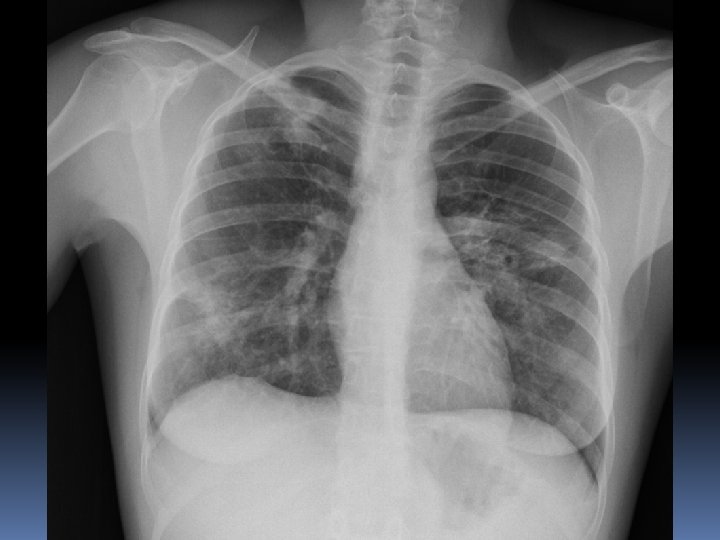

Un mes mas tarde……. .

Desde AP: Laboratorio: puede haber anemia, linfopenia, eosinofilia, trombocitopenia, hipergammaglobulinemia, aumento de VSG, hipercalcemia e hipercalciuria, alteraciones específicas de órganos afectados. En 50 -80% de pacientes se detecta un aumento de la enzima conversora de angiotensina (secretada por fagocitos del granuloma), lo que indica un estadio activo. Hacer serologías para posibles diagnósticos diferenciales. Radiografía de tórax: el 90 -95% de los pacientes tiene alguna alteración radiológica en tórax; lo más frecuente es observar un patrón intersticial retículo-nodular y/o adenopatías hiliares bilaterales. Otros hallazgos posibles son: calcificaciones hiliares “en cáscara de huevo”, cavitación, bronquiectasias, derrame pleural unilateral (exudado linfocitario), cardiomegalia, hipertensión pulmonar. En caso de eritema nodoso con radiología normal y etiología no filiada es conveniente repetir el estudio radiológico al mes.